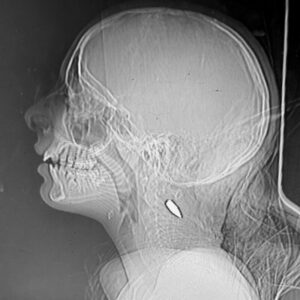

Dziewczynka została trafiona metalowymi odłamkami, prawdopodobnie pochodzącymi z broni fragmentacyjnej. Metal wbił się pod jej nosem i przebił jej głowę. Nie przeżyła. Mark Perlmutter Dziewczynka została trafiona metalowymi odłamkami, prawdopodobnie pochodzącymi z broni fragmentacyjnej. Metal wbił się pod jej nosem i przebił jej głowę. Nie przeżyła. Mark Perlmutter

Dziewczynka została trafiona metalowymi odłamkami, prawdopodobnie pochodzącymi z broni fragmentacyjnej. Metal wbił się pod jej nosem i przebił jej głowę. Nie przeżyła.Mark Perlmutter

Dziewczynka została trafiona metalowymi odłamkami, prawdopodobnie pochodzącymi z broni fragmentacyjnej. Metal wbił się pod jej nosem i przebił jej głowę. Nie przeżyła.

Mark Perlmutter